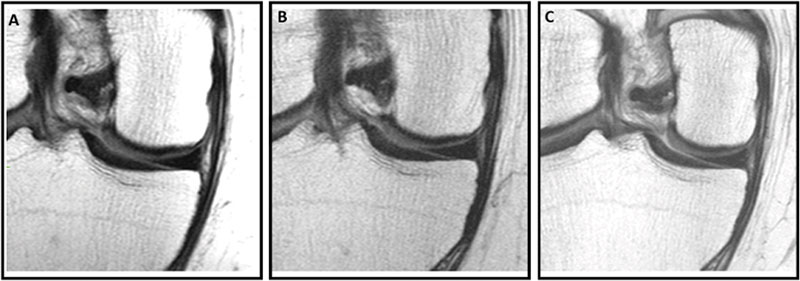

Knee MRI scans in a 57-year-old male participant in the Osteoarthritis Initiative who was administered a hyaluronic acid (HA) injection. Coronal intermediate-weighted knee MRI scans obtained (A) 2 years before injection, (B) at the time of injection, and (C) 2 years after injection show a well-preserved medial femoral cartilage, indicating a stable medial femoral cartilage through the pre- and postinjection time points. The medial femoral cartilage appears well-preserved across all three time points, suggesting no structural deterioration following the HA injection. These findings indicate stable cartilage morphologic structure during the 4-year observation period.